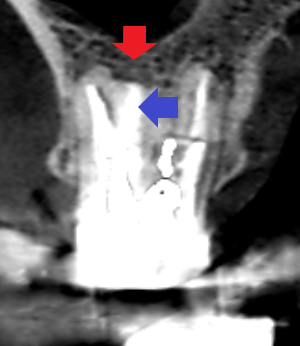

同じく上顎第一大臼歯の冠状断のCT画像の歯根分岐部に膿の影がみられます。髄床底にパーフォレーションがありました。

精密根管治療6カ月後の経過観察時の冠状断のCT画像です。青い矢印の先にあった未治療だった根管が根の先まで根管充填されています。赤い矢印の先にあった膿の影が消失し歯槽骨が再生しています。

精密根管治療6カ月後の経過観察時の冠状断のCT画像です。青い矢印の先にあったパーフォレーションによる膿の影が消失しています。